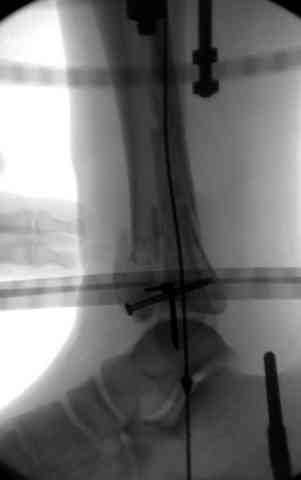

Снова приветствую вас, коллеги. К моменту вступления в обсуждение аксакалов, операция была, увы, выполнена(31.10.07.) Начали с доступа к наружной лодыжке, произвели ее фиксацию спицами, развернули кусок заднего края, наложили дистрактор, затем произвели дистракцию, фиксацию спицами дистального эпиметафиза б/бк,Рентгено-контроль. синтез наружной лодыжки 1/3пластиной. из двух коротких разрезов сформирован канал под медиальную тибиальную пластину LCP. Края ран ушиты без натяжения. Прочувствовать жесткость фиксации винтами с угловой стабильностью не удалось, поэтому дистрактор оставлен на энное время.

На представленных R-снимках не окончательный вид после остеосинтеза. Дистальная опора давила на стопу, пришлось ее сместить проксимально, в рез-те чего, она закрыла щель сустава, последние снимки не информативны.

Дистальные винты как-то чуть не все идут не в дистальные отломки, а в зону перелома. И действительно, присоединяюсь к вопросу Якова - в диафизе так и оставили 1 винт?

И вправду. В аппарате - практически идеальная для данного случая репозиция (браво!). Пластинка только помешала( в плане возможных осложений), так как не добавит стабильности после снятия наружного фиксатора, (что не скоро будет). Спицы в аппарате, пожалуй, только добавят проблем с дальнейшим лечением (проксимально - я - за стержни). Вполне приемлимо бы было, добившись репозиции в дистракторе, провести спицы с упорными под ЭОП, срепонировать отломки и оставить как есть. А вероятный артродез произвесть в аппарате потом.